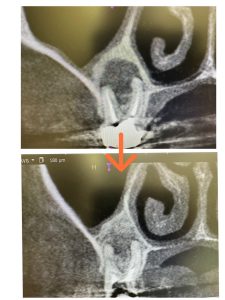

病巣改善❗️

非常に良く治ってきている!

画像みれば分かるが、骨化が著しい、次回MTA根充

ここまで来れば、自然治癒力で治ります

ポートランドセメント効能PH12.4強アルカリ性もあるからね💪